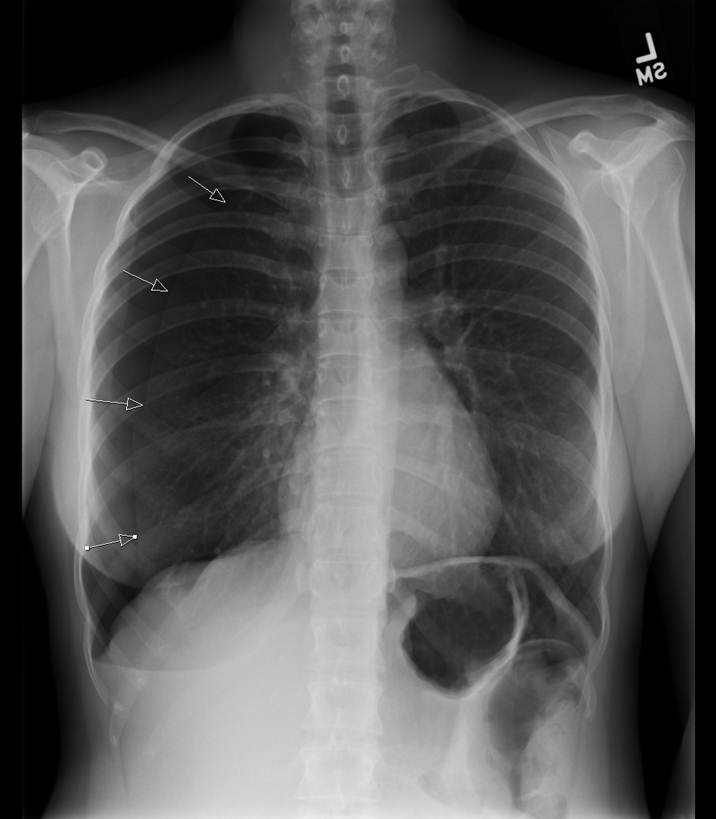

As with any procedure, informed consent is obtained and time-out conducted, including confirmation of identity and laterality with imaging studies (Figure 1). The site of insertion is the anterior chest wall, mid-clavicular line at the second intercostal space. A routine prep and drape is conducted (Figure 2). Next, local anesthetic (1% lidocaine) is infiltrated into the anterior 2nd intercostal space, staying just on the superior aspect of the rib. Typically, the authors have done this with local anesthetic (with minimal to no intravenous narcotics), and it is well tolerated (Figure 3). Once local anesthetic has been infiltrated, the introducer needle and catheter are used to aspirate air as the needle and catheter are advanced into pleural cavity (Figure 4). Once in the pleural cavity, a flexible guidewire is advanced into the pleural space (Figure 5). A small skin incision with a #11 scalpel facilitates passage of the dilator and subsequently the drain (Figure 6). The dilator is slowly advanced over the guidewire just enough to enter the pleural cavity. It is important to always maintain control of the end of the guidewire (Figure 7). Following dilation, the dilator is removed, and the percutaneous drain is advanced over the guidewire until the holes are all in the pleural cavity (Figure 8). Once the catheter is in the pleural cavity, tension on the drawstring locks the pigtail catheter. Finally, the pigtail catheter is connected to a Pneumostat valve or other water seal/collection device (Figures 9 & 10).